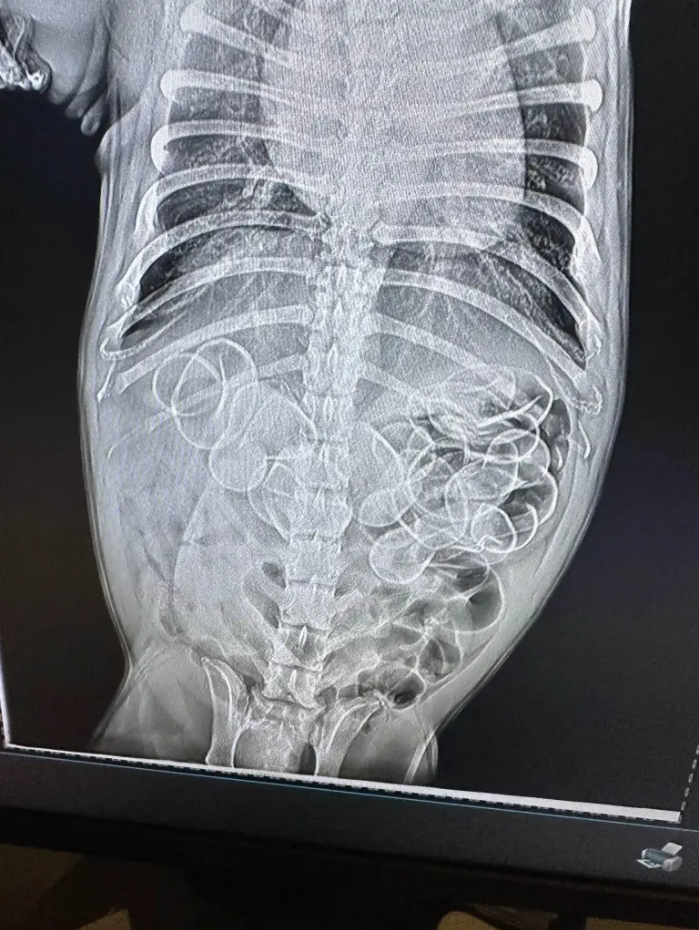

Франц бульдог нохойн эзэн Лю хэмээх бүсгүй гэрт нь байсан резинэн нугаснууд алга болсон байгааг анзаарчээ. Ундаа худалдаж авах үед үнэгүй өгдөг эдгээр нугаснуудыг нохой нь залгисан байж магадгүй хэмээн бодсон Лю яаралтай мал эмнэлэгт ханджээ. Мал эмнэлгийнхэн нохойн ходоодны рентген зургийг аваад цочролд оржээ.

Эмч нар түүний ходоодонд дор хаяж 5 нугас байгаа хэмээн тооцоолон яаралтай хагалгаа хийхээр болсон бөгөөд хагалгааны үеэр нийт 11 нугас гарган авчээ. Резинэн материал бүхий зүйлс залгих нь маш аюултай байдаг тухай Pet Educate мэдээлжээ.